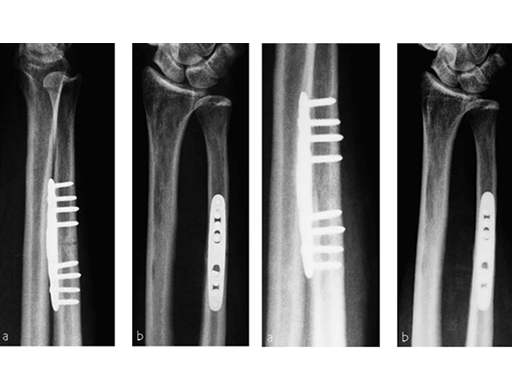

A 69-year-old female patient had suffered a right distal radius fracture one year earlier, and received conservative management. Symptoms included pain and impaired function about the wrist and forearm, with decreased forearm rotation. Painful DRUJ (DASH: 34, PWRE: 29).

Case 2: Painful ulno-carpal abutment

A 32-year-old man suffered torsional trauma about the right wrist, with TCFF rupture. A failed arthroscopic repair had taken place. Constitutional ulna plus. Symptoms included pain and impaired function about the wrist and forearm. Painful DRUJ (DASH: 22, PWRE: 21).